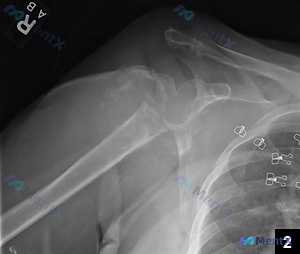

影像初步结果:右肩部X光提示——

- 肱骨近端复杂性骨折:累及解剖颈及大结节,伴有明显移位和多发骨折碎片

- 盂肱关节脱位:肱骨头与关节盂失去正常解剖对位

- 周围软组织肿胀

📋答案:本病例核心矛盾是“严重的肱骨近端粉碎性骨折伴盂肱关节脱位”与“无明确外伤史”。从全局判断,最可能的根本原因是**脊髓空洞症导致的神经源性关节病(Charcot肩)**。